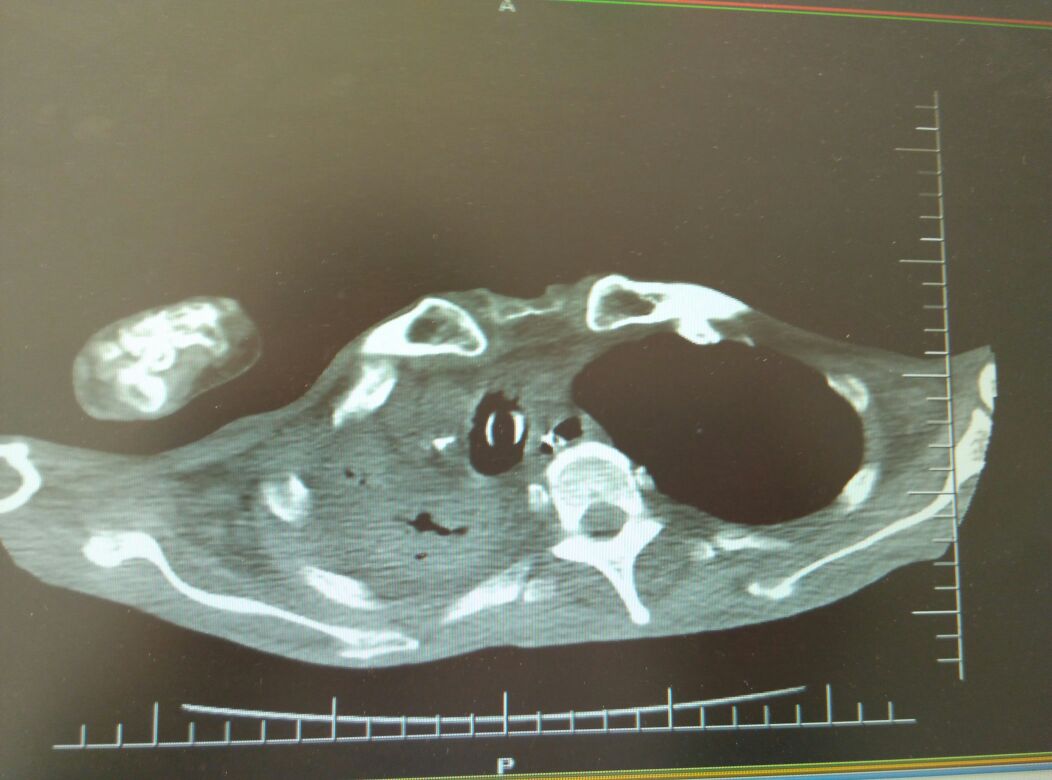

气管插管

男,86岁,慢性咳嗽咳痰30年,加重3天,伴发热,喘息。